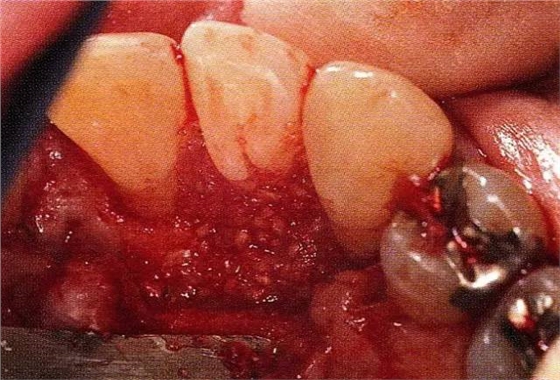

案例3針對(duì)3壁性垂直性骨缺損使用非吸收性膜進(jìn)行再生治療,再翻瓣時(shí)進(jìn)行骨形態(tài)修整的病例。

▲圖7-1左下6近中可觀察到3壁性垂直性骨缺損。此病例考慮到齦瓣供血關(guān)系,在前磨牙部位進(jìn)行了減張切開,沒有進(jìn)行縱切開。并利用刮治器、牙周外科用車針進(jìn)行了徹底的骨缺損部位搔刮。